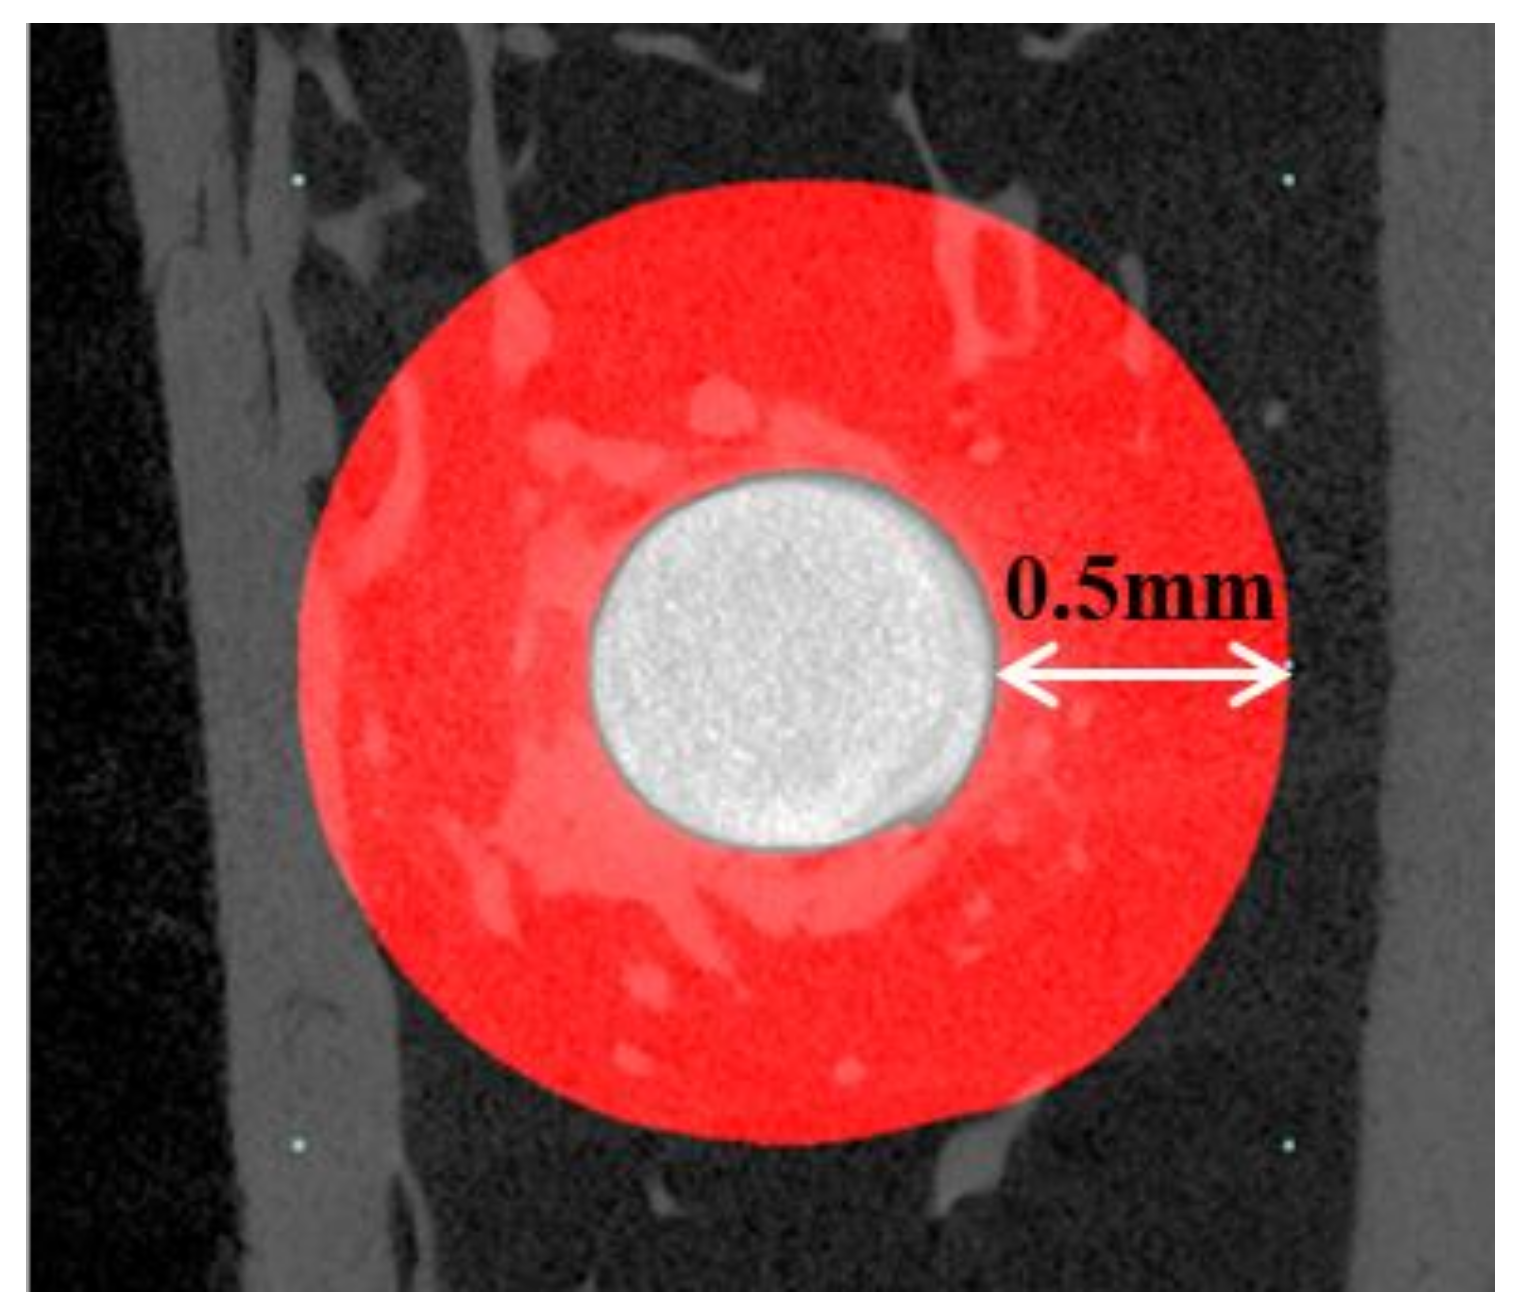

2.2.2. Micro-Computed Tomography (μCT) Findings

4.3.3. Micro-Computed Tomography (μCT) Analysis